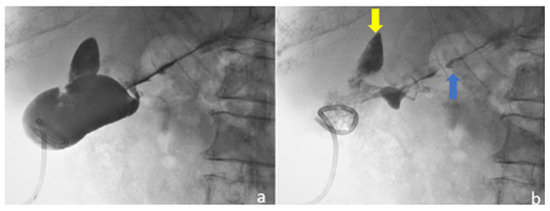

2.1. Case 1